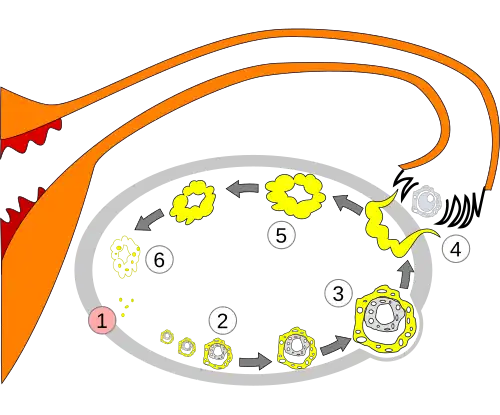

The corpus luteum develops from an ovarian follicle during the luteal phase of the menstrual cycle or oestrous cycle, following the release of a secondary oocyte from the follicle during ovulation. The follicle first forms a corpus hemorrhagicum before it becomes a corpus luteum, but the term refers to the visible collection of blood, left after rupture of the follicle, that secretes progesterone. While the oocyte (later the zygote if fertilization occurs) traverses the fallopian tube into the uterus, the corpus luteum remains in the ovary.

If the egg is fertilised and implantation occurs, the syncytiotrophoblast (derived from trophoblast) cells of the blastocyst secrete the hormone human chorionic gonadotropin (hCG, or a similar hormone in other species) by day 9 post-fertilisation.

Human chorionic gonadotropin signals the corpus luteum to continue progesterone secretion, thereby maintaining the thick lining (endometrium) of the uterus and providing an area rich in blood vessels in which the zygote(s) can develop. From this point on, the corpus luteum is called the corpus luteum graviditatis.[17]

The introduction of prostaglandins at this point causes the degeneration of the corpus luteum and the abortion of the fetus. However, in placental animals such as humans, the placenta eventually takes over progesterone production and the corpus luteum degrades into a corpus albicans without embryo/fetus loss.

Order of changes in ovary -